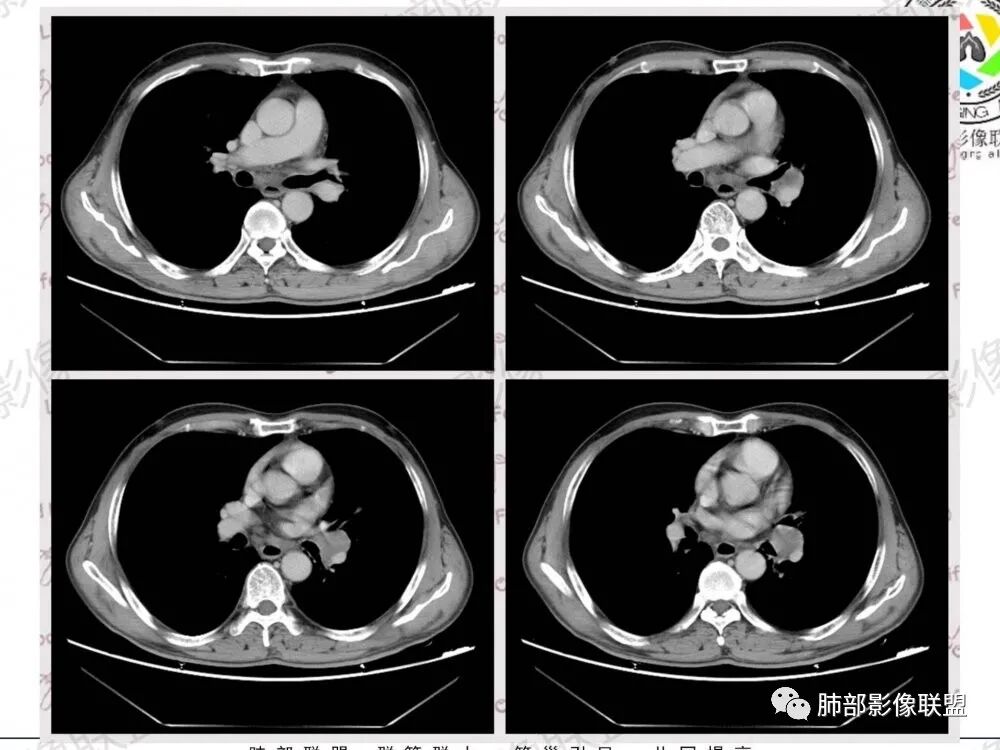

1.左肺门及纵隔见异常增大淋巴结,部分融合,不均匀轻度强化,未见明显坏死。

肿大淋巴结与纵隔血管等结构“无缝”贴合。

2.纵隔增宽但依旧居中。

2.患者声音嘶哑是巧合吗?

声音嘶哑、左侧声带固定等是左肺上叶肺癌最具代表性的临床表现之一,有经验的耳鼻喉科医生常会因此要求患者排查肺部。

左肺上叶肺癌在主动脉窗附近侵犯阻击远道而来的左侧喉返神经是其常见套路。

临床实践中,除肺癌外,较少其他病灶能够造成左侧声带麻痹。

注意是左侧喉返神经!右侧喉返神经并未绕行胸廓入口以下。

2、小细胞癌恶性程度高,发展迅速,转移发生早;常有纵隔淋巴结的明显增大融合(发生率达96.5%),呈“冰冻纵隔”,淋巴转移常为逐站的连续性转移;亦有血行转移,脑、肾上腺、肝、胰、骨髓等;转移灶常比原发灶大得多,即“娘小崽大”特点;

3、因其对血管、支气管破坏程度轻,故坏死相对较轻,极少出现空洞;小细胞肺癌支气管壁肥厚、管腔狭窄,但表面可有正常黏膜,除非狭窄非常严重,否则不会引起支气管刺激症状,故该症状对其早期诊断无意义;受累支气管末梢侧阻塞性炎症少。